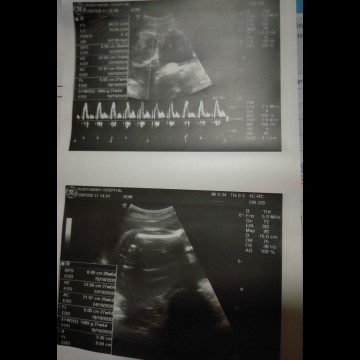

āđāļāđāļāļāļđ āļŦāļĨāļāļĨāļđāļ #āļāļāļāļđāđāļāļāļēāļ§āļāđāļāļĩāļĄāļāļļāļĨāļēāļŦāļāđāļāļĒāļāđāļ° ðĨ°ð§ļ